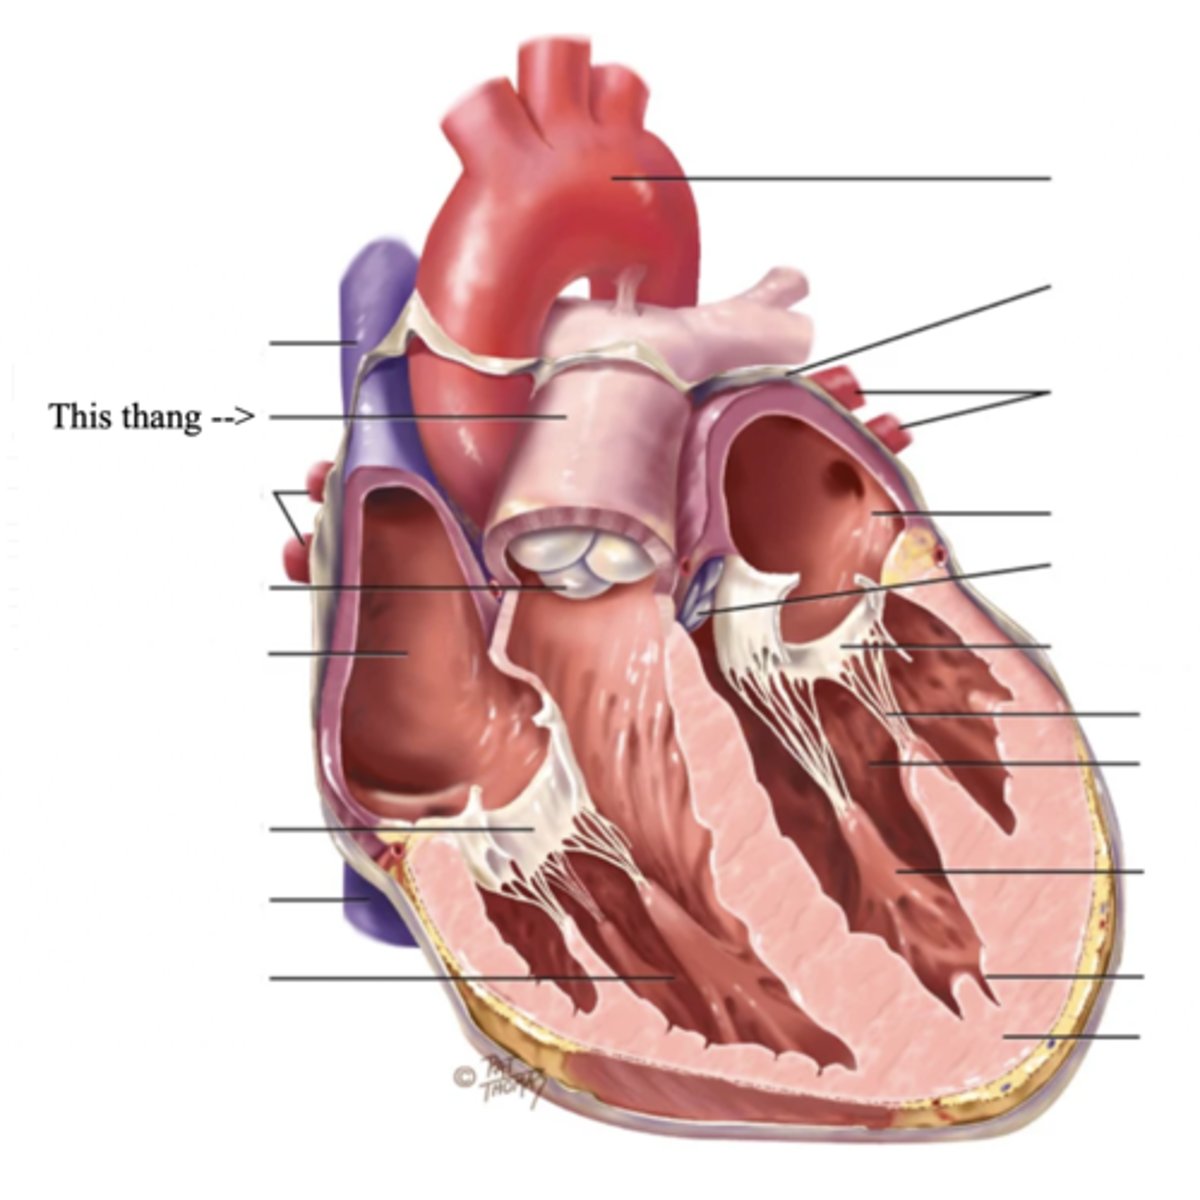

Anatomy of the Heart

Ventricle (2)

The thick walled muscular pumping chamber of the heart located at the bottom chamber of the heart

Semilunar Valves (SV) (2)

Valves located between the ventricles and the pulmonary arteries and aorta

The 2 Semilunar Valves of the Heart

- Pulmonic

- Aortic

Pulmonic Valve

The SV valve of the right side of the heart

Aortic Valve

The SV valve of the left side of the heart

The 4 Great Vessels of the Heart

Aorta

The largest artery in the body which carries oxygenated blood from the heart throughout the body